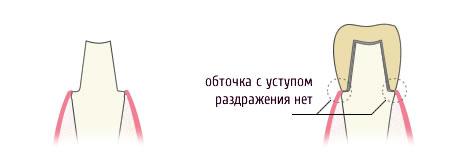

Металокераміка з плечової масою

Плечова маса на металокераміці робиться для підвищення естетичних якостей протеза і виготовляється з зовнішньої (видимої) сторони, для уникнення просвічування металу через ясна. Зуб під металокерамічну коронку з плечової масою обточується з уступом. Уступ вимагає від лікаря спеціальних навичок і призначається для запобігання подразнення контактної зони кераміка-метал-ясна. Якщо ви уважно подивитеся на малюнок, то інтуїтивно зрозуміло, що обточування зуба з уступом краща. Вартість і роботи і самої металокерамічної коронки в цьому випадку вище.